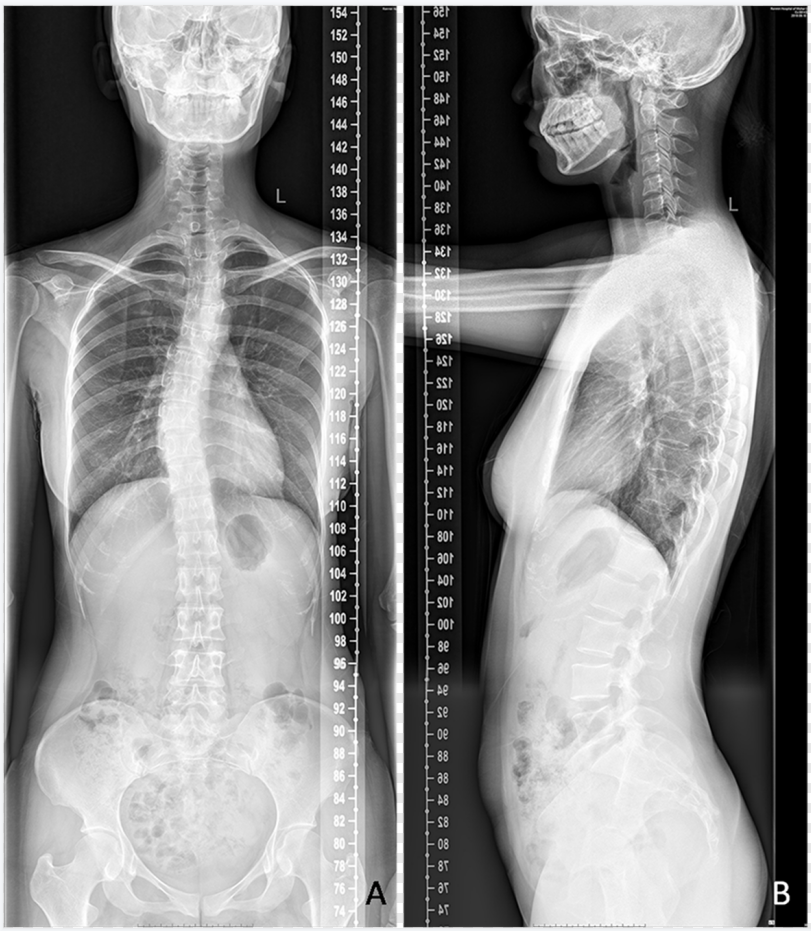

是在自动控制程序模式下,一次性采集不同位置的多幅图像,然后由计算机采用精确配准技术进行无缝全景拼接,合成为大幅面X线图像。临床上主要应用于骨关节系统疾病,如脊柱侧弯矫形、下肢矫形及人工关节置换等,可显示病变范围和全脊柱或肢体的整体受力状态,常见体位包括脊柱与双下肢全长摄影(图5、图6)

dr数字怎么用数字化X线摄影术(DR)_https://www.jmylbn.com_新闻资讯_第7张

图5  脊柱侧弯脊柱全长拼接